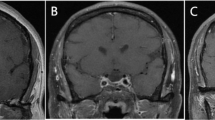

Ten models for each type of data input (T1-weighted, contrast-enhanced T1-weighted or both) were established to discriminate PPT and NPPT as a model group. The performance of these model group in validation and the nested cross-validation were summed in Table 2 and Supplementary Table 5, respectively. Among the PPTs in the validation cohort, 2 of 9 cases were misclassified: one PC (MR image provided in Supplementary Fig. 1) and one GCT. Model group based on contrast-enhanced T1-weighted features alone performed best in the validation cohort with accuracy of 0.786, precision of 0.929, specificity of 0.778, sensitivity of 0.788, and AUC of 0.818 (Fig. 2). The performance of model group based on T1-weighted features alone was poor in the nested cross-validation (AUC = 0.697) and even worse in validation cohort (AUC = 0.593). Performance of model group based on the combination of the two features described above (AUC = 0.803) was sightly inferior to that based on contrast-enhanced T1-weighted features alone in validation cohort. The clinical features were added to the best performing input data (contrasted-enhanced T1-weighted features alone) and the above modeling and validation were repeated. However, the clinical features were discarded in the dimension reduction process of each inner loop of nested cross-validation, so that the results were similar to those only used contrast-enhanced T1-weighted features as input and changed the random seed, so they would not be described in detail.

The models based on those features extracted from contrast-enhanced T1-weighted images had a better predictive performance than those models only based on T1-weighted features, suggesting that PPTs and NPPTs on contrast-enhanced images may have more significantly predictive values. Contrast-enhanced images of craniopharyngiomas have better discrimination, thus it generally manifests as a heterogenous mass with mixed cystic and solid multiloculated, and the contrast enhancement is present within solid components and as rim enhancement of the cystic areas32. PitNET presents a mild to moderate contrast enhancement, which is generally less than normal pituitary tissue. Most PPTs show homogeneous enhancement5 (especially in 80.5% of pituicytomas3) and are easily confused with PitNETs. This may explain the misclassification of one PC case in our cohort, which exhibited atypical imaging features: suprasellar extension was absent, and heterogeneous enhancement was observed. Radiomics features may provide discriminative power beyond that of human readers and most of the 9 key features were significantly different between the PPTs and NPPTs groups. For GLCM-based features, elevated Cluster Shade and its derived features suggest increased skewness in gray-level distribution, potentially linked to focal T1 hyperintensity and heterogeneous enhancement in PPTs. Elevated Cluster Prominence further reflected greater intensity variability in PPTs, possibly linked to histopathological heterogeneity. The Square feature derived from High Gray Level Run Emphasis was based on GLRLM, and indicated there were greater concentration of high gray-level values in the images of NPPTs. The two derived features of Large Dependence High Gray Level Emphasis were based on GLDM and indicated the joint distribution of large dependence with higher gray-level values was different between PPTs and NPPTs. Specifically, the elevated feature values in PPTs suggested clustered high-intensity voxels, potentially corresponding to cystic components or fluid accumulation observed on MRI. In contrast, NPPTs exhibited lower values due to more dispersed high-intensity regions. These subtle texture differences serve as the basis for discriminating PPTs and NPPTs.